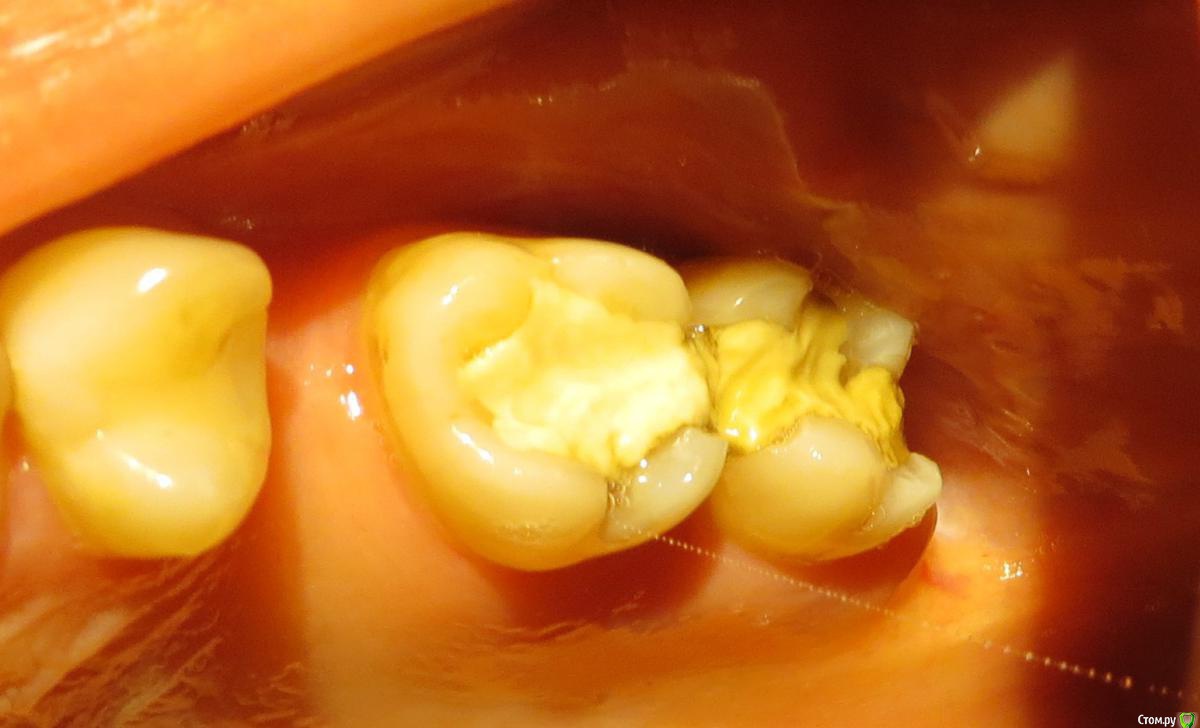

anaG2011 Опубликовано 27 июля, 2017 Поделиться Опубликовано 27 июля, 2017 (изменено) Здравствуйте!На верхних 6 и 7 зубах стояли пломбы с 2001г. Откололся кусочек 7ки.Врач высверлил старые пломбы. Каналы не вскрывали. На 7ке поставил "лечебную прокладку".Закрыл зубы временными пломбами. На холод-горячее-накусывание не реагируют. Скажите, пожалуйста, каким способом предпочтительнее восстановить 6 и 7 :пломбами или керамическими вкладками ?Какие минусы каждого из вариантов?(антагонист 7ки - недепульпир. зуб с пломбой 2001г.) Заранее спасибо. С временными пломбами: http://s016.radikal.ru/i337/1707/21/0e977cd9dd43.jpg До начала лечения: http://i057.radikal.ru/1707/b8/d717547654e5.jpg Изменено 27 июля, 2017 пользователем anaG2011 Ссылка на комментарий